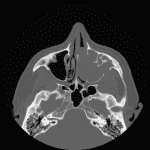

Age: 54

Sex: Male

Indication: Left nasal mass

Inverted Papilloma

- Inverted papilloma

Expansile mass in the left maxillary sinus with associated sinus wall remodeling and dehiscence and bulging into the nasal cavity and retroantral fat with obstruction of the left ostiomeatal unit. Hyperostosis about the left infraorbital canal is typical for inverted papilloma and represents the likely site of tumor origin.

Expansion of the medial aspect of the left frontal sinus with polypoid soft tissue markedly thinning the intersinus septum and bulging into the right frontal sinus, which could represent contiguous extension of the maxillary sinus mass versus separate mass/mucocele.

No definite dehiscence through the inner table of the calvarium.